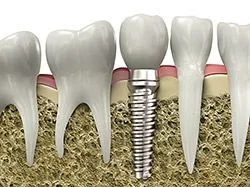

An implant is a synthetic tooth root in the shape of a post that is surgically placed into the jawbone. The “root” is usually made of titanium: the same material used in many replacement hips and knees, and a metal that is well-suited to pairing with human bone. A replacement tooth is then fixed to the post. The tooth can be either permanently attached or removable. Permanent teeth are more stable and feel more like natural teeth.